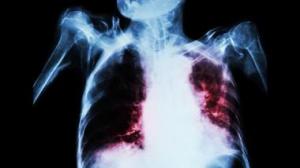

Представители Всемирной организации здравоохранения заявили, что наиболее смертоносным является туберкулёз.

В организации заявили, что несмотря на максимальное усилие по предупреждению распространения болезни, лишь в 2017 году от нее погибли более 1,6 миллионов человек, а количество зараженных и вовсе перевалило за 10 миллионов.

В ВОЗ также отметили, что благодаря совместным усилиям мирового сообщества, начиная с 2000 года удалось предотвратить смерть от заболевания около 54 миллионов человек. Количество же новых случаев заражения ежегодно сокращается на 2 процента, что относительно неплохо в условиях нынешних реалий.

По мнению представителей ВОЗ, проблемой является и тот факт, что все большее число людей в мире заболевают резистентной формой туберкулеза, когда болезнь не реагирует на рифампицин, который является основным противотуберкулезным препаратом.